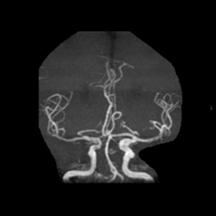

脑动脉开窗畸形通常在尸检或者影像学检查时被发现。CTA和MRA不仅能够无创地显示开窗畸形的位置、形态和毗邻结构,还能显示伴发的其它病变,是脑动脉开窗畸形2种最佳的诊断方法。当脑动脉开窗畸形难以跟动脉夹层进行鉴别时,可以考虑行脑血管造影检查,进行三维重建便可进一步帮助鉴别。